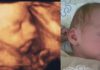

Forside Billeder og gallerier 3D scanning uge 14+6

uge 14+6

Lagt på siden af Mette

D. 27. juni 2007

fra 3d scanning i 26. uge til baby